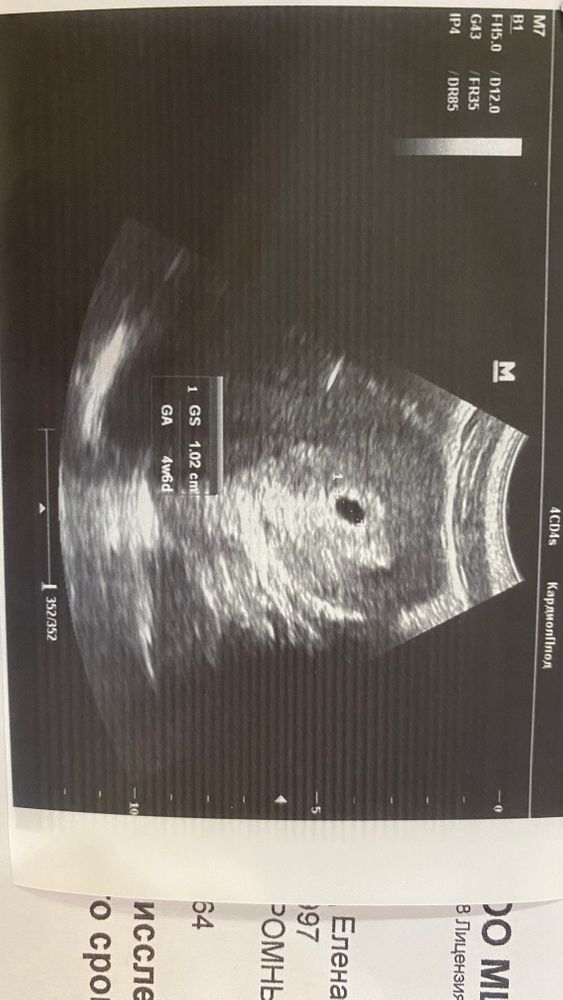

У вас все хорошо. Развивающаяся маточная беременность и хорошо видное ПЯ.

Элиза Вебер, 5 недель. Маточная все хорошо Изображение

Lychek, была сегодня у врача. 5 недель нам. Маточная. Все хорошо

Елена, ну что, нам оказывается 5 неделек только и все хорошо Изображение